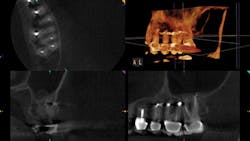

The CBCT scan reveals palatal root resorption.